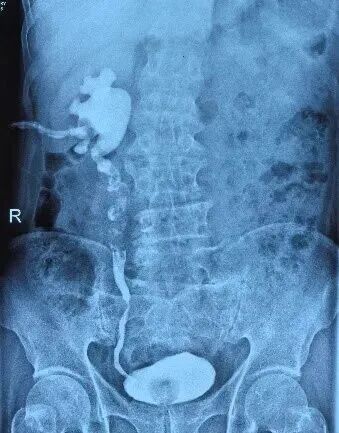

Upper urinary tract imaging and contrast-enhanced CT with three-dimensional reconstruction demonstrated marked tortuosity and dilation of the middle and upper segments of the right ureter, accompanied by multiple annular strictures and extensive intraluminal filling defects, measuring approximately 7–8 cm in length.

Preoperative antegrade and retrograde urography of the patient